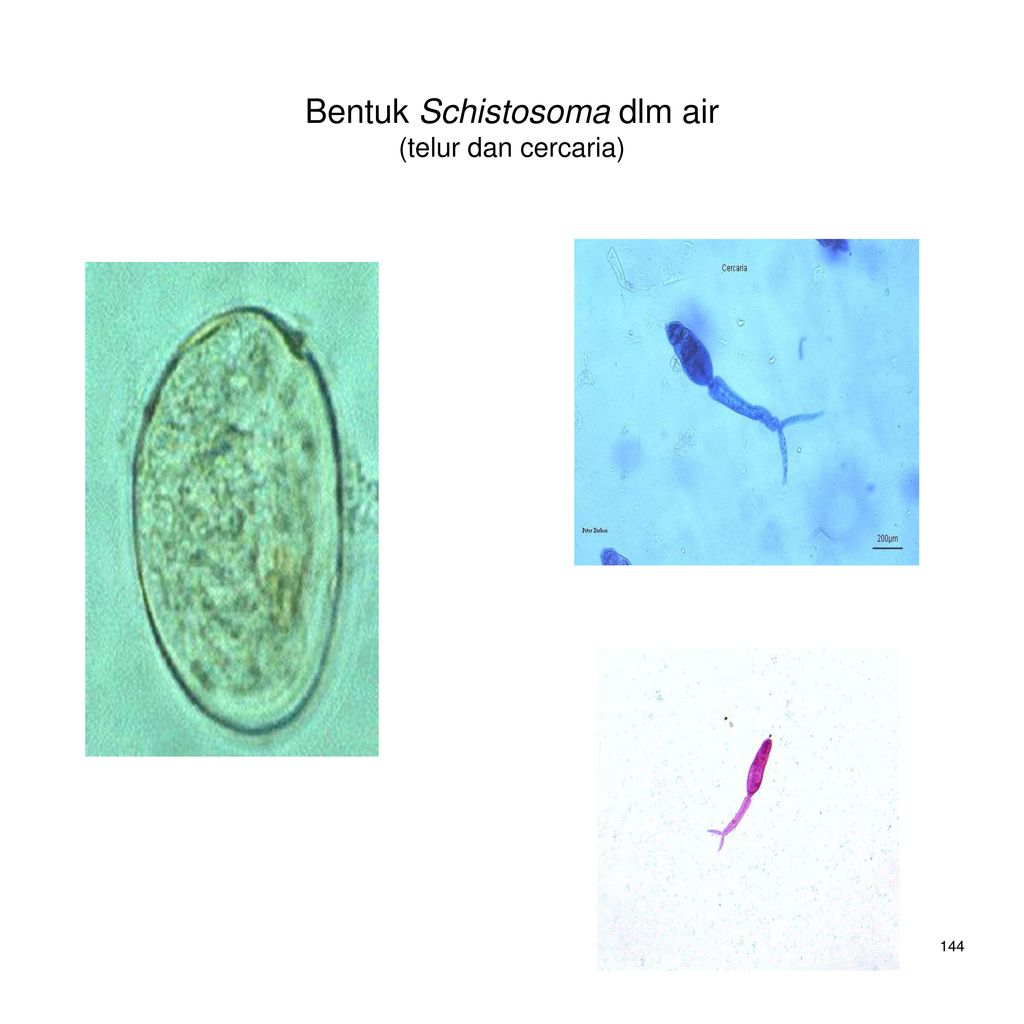

Шистосомоз: что нужно знать о паразитах